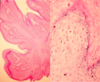

What is this?

Breast abscess: Fibrous capsule with inflammatory infiltrates